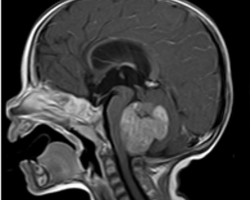

Un enfant de 6 ans est emmené par ses parents aux urgences pédiatriques pour des vomissements incoercibles. L’enfant se plaint depuis plusieurs semaines de céphalées, mal soulagées par la prise de paracétamol.